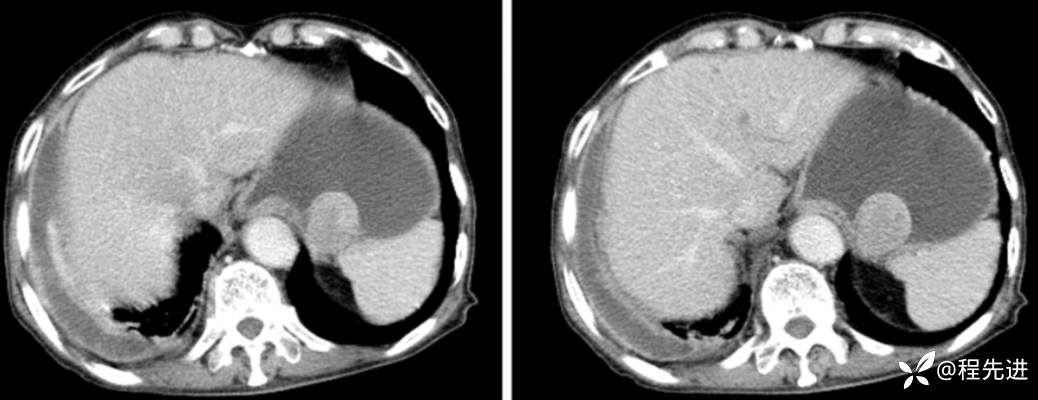

CT

平扫

动脉期